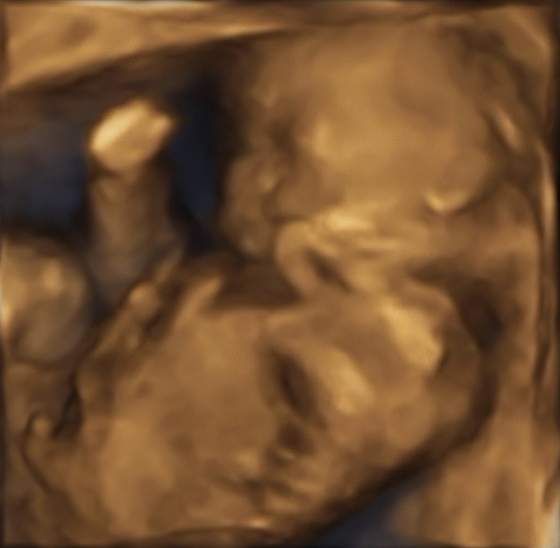

Ja po wizycie, ale nic nowego - wszytsko w porzadku. Nawer nie ma co opisywac w watku wizytowym. Czekam na usg polowkowe w sobote. Wtedy sie dowiemy, czy rezerowac ostatecznie miejsca nad Balatonem:-)